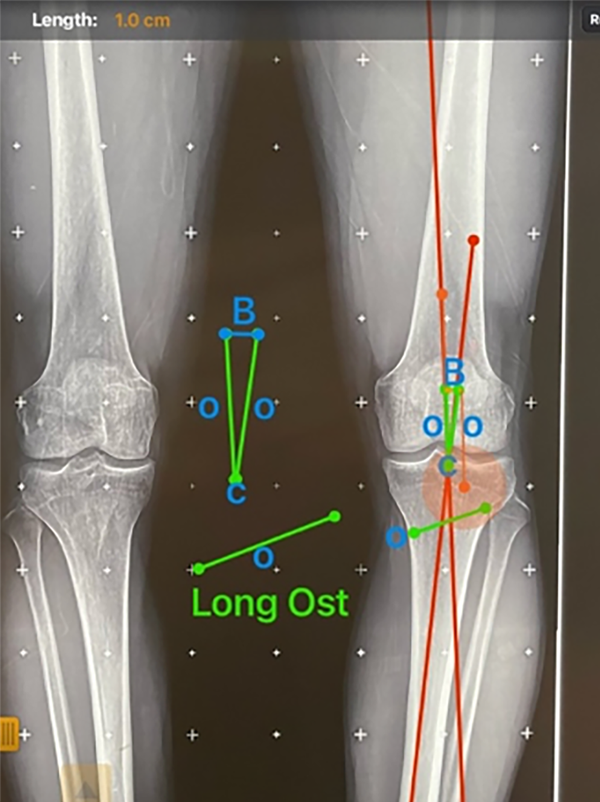

El método de planeamiento que se enumeró y explicó previamente tiene tres formas de comprobarse de forma pre e intraquirúrgica: la primera forma es mediante el software, se mide el espacio al cual se le hizo la apertura y esto da los milímetros de la cuña, que se compara con el resultado de la fórmula trigonométrica que usa la tangente del triángulo (fig. 18). La segunda forma es desarrollada por uno de los autores de este trabajo, conocido como Método Alzate, y consiste en obtener los milímetros de apertura a partir del ángulo de deformidad, al tener la longitud de osteotomía se ubica en el punto de la corrección y se mide la distancia hacia proximal, que formaría el lado de un triángulo, luego la misma medida sería el otro lado del triángulo, y se miden los milímetros del tercer lado del triángulo o su base, y esto debe corresponder al mismo resultado de la tangente del ángulo de corrección multiplicado por la distancia (fig. 19).

Figura 19: Método Alzate: En el planeamiento obtenemos la longitud de la osteotomía, y también se tiene el ángulo de corrección para que el MAD pase por el punto que previamente definimos (50% o 62%), en este caso el 50%, como sabemos que esta intersección de líneas forma el ángulo que debemos corregir, el método Alzate consiste en medir desde este punto la longitud de la osteotomía. En la imagen el punto C (Corrección), y la distancia O (Osteotomía), las medimos en cada una de las líneas, vamos a obtener dos lados de un triángulo isósceles, así que esto es la resolución gráfica de la fórmula trigonométrica. B (Brecha) sería el otro lado faltante, que corresponde a los milímetros de apertura, en este caso, 10 mm.